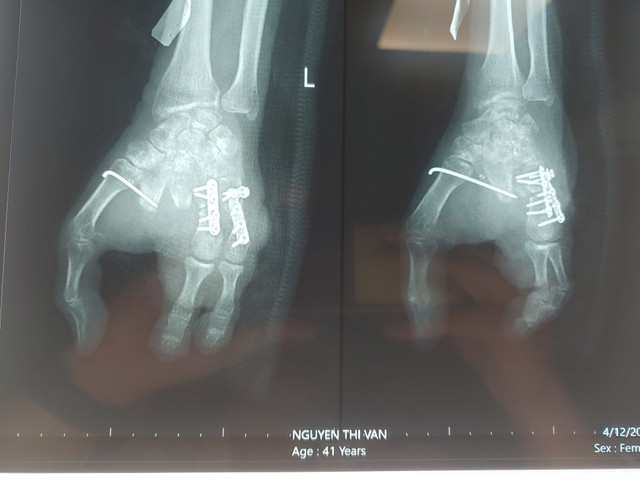

| Hình chụp X Quang sau khi nối ngón tay |

Là người trực tiếp phẫu thuật cho trường hợp bệnh nhân V., Bác sĩ CK1 Võ Thành Nhơn – Khoa Phẫu thuật chi trên, Bệnh viện Quân y 175 cho biết, ca phẫu thuật đã kéo dài 6 giờ. Kíp mổ đã đưa ra hướng kết xương từ ngón chân lên bàn tay, khâu nối mạch máu, dây thần kinh, gân cơ từ 2 ngón chân 2,3 của bàn chân trái với mạch máu 2 ngón tay thứ 4,5 của bàn tay trái giúp phục hồi sự sống của ngón tái tạo. Các công đoạn ghép ngón tay này gồm nhiều kỹ thuật, việc khâu nối mạch máu và thần kinh ở những trường hợp này rất phức tạp.

Đối với trường hợp của bệnh nhân V., việc mất đi các ngón tay khiến sinh hoạt của bệnh nhân rất khó khăn. Vì vậy, sau 3 tháng khi phần mềm tay phải ổn định, không có dấu hiệu nhiễm trùng, bệnh lý nền được kiểm soát tốt, các bác sĩ đã phẫu thuật ghép lấy ngón chân thứ 2,3 của bàn chân trái đưa lên ngón tay 4,5 của bàn tay trái nhằm tạo cung cầm nắm giúp bệnh nhân.